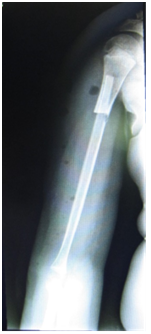

An 11-year-old male looked for medical assistance due to pain and swelling in his right arm, which had started three months earlier. Patient showed no other signs or symptoms. Swelling and warmth in the middle and distal thirds of the patient’s arm were found in physical examination. All laboratory tests fell within normal values, i.e., within reference range values, except for the LDH level, which was 280 U/L (normal LDH levels range from 100 U/L to 190 U/L). Radiological findings (Figures 1 & 2) showed permeable lytic lesions and “onion skin” periosteal reaction in the right humeral shaft. Thus, needle bone biopsy was indicated. Biopsy confirmed the presumptive diagnosis of Ewing’s sarcoma. After staging, which excluded the dissemination of the disease, the treatment protocol was started, which was neoadjuvant chemotherapy, associated to surgery and adjuvant chemotherapy. The oncologic resection procedure was performed 5 (five) months after the diagnosis - arthrotomy of the right elbow and humerus osteotomy at 22cm from the proximal extremity. In order to cover the bone defect, we opted for reconstruction with ipsilateral vascularized fibular autograft - a segment of 23cm of the right fibula with a vascular pedicle to the fibular artery has been resected. The medical team then performed a termino-lateral anastomosis to the brachial artery and termino-terminal anastomosis to the basilic vein (Figure 3). Clamping of the fibular graft under pressure in the humeral medullary cavity was the method of choice for graft fixation in the proximal end, and distally, the fixation was obtained with capsulorrhaphy of the head of the fibula to the elbow joint (Figure 4). The choice not to use a plate for proximal fixation was made in the intraoperative period due to the satisfactory stability obtained with the clamping of the graft in the humerus. Patient presented good postoperative evolution, with a satisfactory range of mobility in the limb which underwent surgery, and high patient-satisfaction ratings (Figure 5). Two fractures of the grafted bone segment (the first occurred 13 months after the surgery and the other one 32 months after the surgery) were the postoperative complications reported. Both of them were satisfactorily handled with conservative treatment, i.e., full cast.

Figure 4 Anteroposterior view of the arm after the surgery. We can see the clamping of the fibula in the proximal medullary cavity of the humerus.